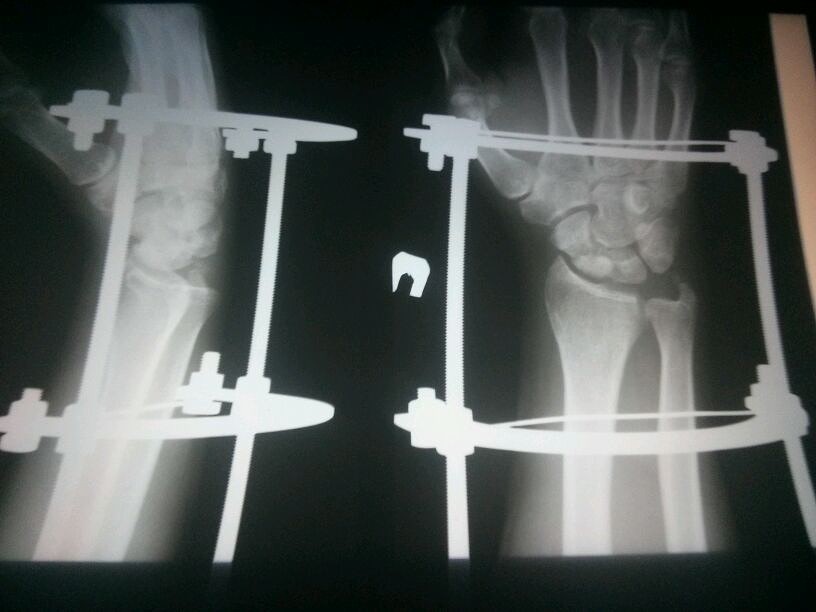

Да не.. Пластина - фигня, по сравнению с этим оборудованием.. Как с ним можно было жить три месяца, я даже представить не могу

Потом 2 мес в гипсе (только гипс был полностью нога до складки бедра, пальчики открыты были ахахах)

Потом сняли, сделали снимок и еще 2 месяца ходила, потом на костыликах прыгала